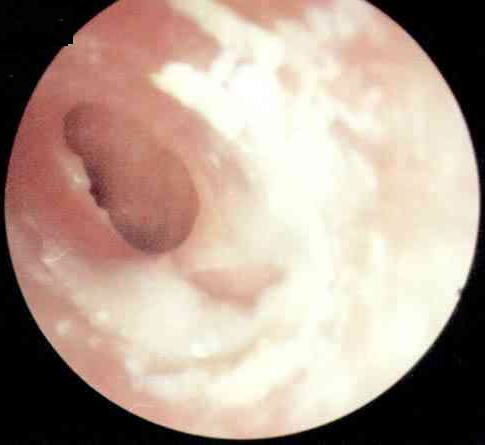

分泌性中耳炎是由于细菌等微生物感染引起的耳部急性炎症,它以鼓室内积液引起听力减退为主要特征。在秋冬季节,它是比较常见的耳部疾病之一。是什么原因引起分泌性中耳炎的呢?耳科的张全安教授指出需从耳部的解剖结构说起。

人们常说人的七窍是相通的。耳朵通过咽鼓管与鼻咽部相通。咽鼓管可以调节耳内的压力,以此与大气压保持平衡,其外还有防御、清洁的功能。在秋冬季,日夜温差比较大,常会诱发上呼吸道感染,炎症波及咽鼓管时,耳内往往会形成负压,这时会产生耳闷的感觉。耳内的黏膜受负压影响分泌较多的液体,并由于咽鼓管功能障碍不能及时排出,积在耳内产生听力下降,耳朵里有水泡声,有时还会感到耳痛。

医生指出:分泌性中耳炎如果未得到及时的治疗,耳内的液体未完全吸收,会导致鼓室硬化、粘连性中耳炎、胆固醇性肉芽肿等继发疾病,这些疾病的治疗将比分泌性中耳炎复杂得多。患者由于听力减退,会影响其语言的发育和学习,影响与他人交流的能力。